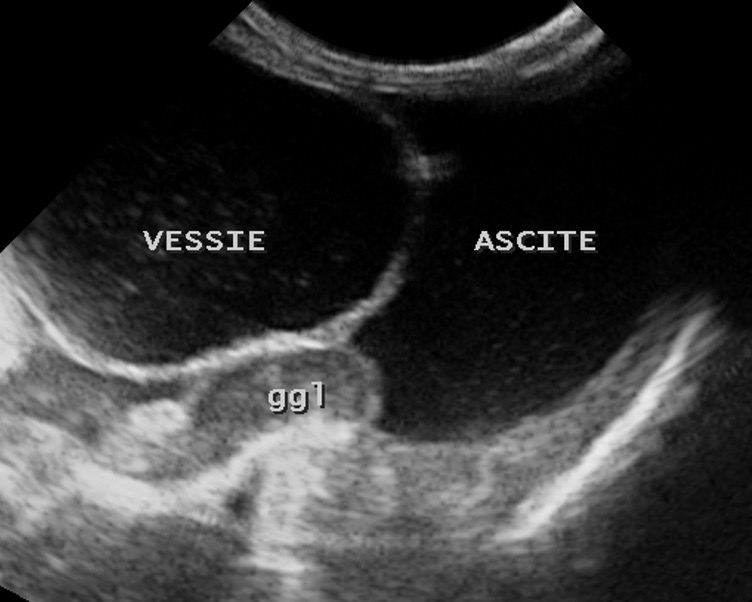

Deux images d’ascite importante chez des chats atteints de PIF : à gauche, seule la mince paroi de la vessie permet de distinguer le liquide à l’intérieur (l’urine) du liquide à l’extérieur (l’ascite). A droite : un rein perdu au milieu du liquide d’ascite ; on remarquera au passage la corticale rénale hyperéchogène, et aussi la présence d’un anneau médullaire (ou « medullary rim », cette ligne hyperéchogène qui suit la jonction cortico-médullaire) marqué : dans une étude portant sur la signification de cette image échographique dans le rein des chats (Ferreira & Coll, 2020), sur 23 chats atteints de PIF, 15 présentaient cet anneau médullaire, le plus souvent épais, et 8 ne le présentaient pas. Pour les auteurs, cette différence permet de conclure à une association significative entre anneau médullaire et PIF. Donc un indice diagnostique intéressant mais bon, ce n’est pas parce qu’on voit un anneau médullaire dans le rein d’un chat que celui-ci a forcément la PIF, et réciproquement !